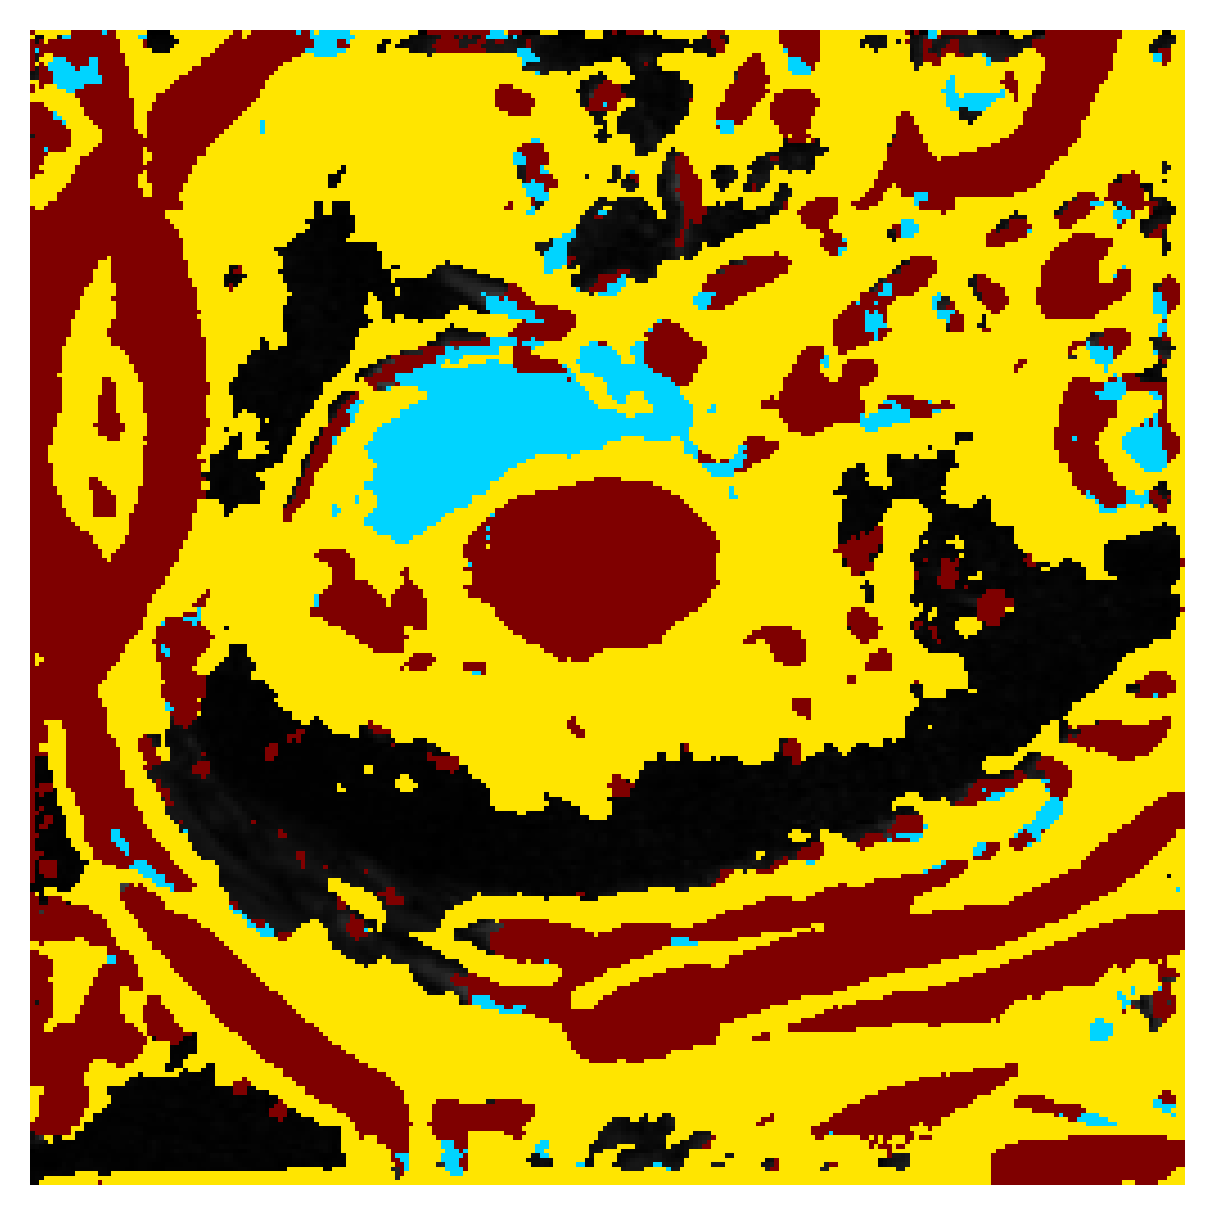

We normalize the volumes and resize the slices to pixels. As the official dataset comes with full annotations, we create a synthetic point ground truth. This is done by first randomly choosing the centers of the point annotations within the class masks, followed by filling an ellipse with axes lengths of and (in pixels) around each center. The intersections of these elliptic discs with the underlying full annotations are then used as our point ground truth. See Figure 2 for an example of the created weak annotation mask. The point annotations are created for every slice, one for each foreground object present in the slice.